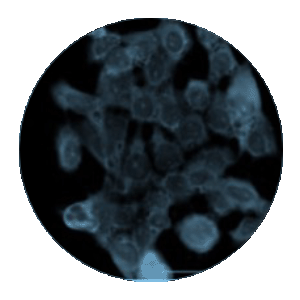

Les réactifs du panel ModDetect PS permettent une visualisation claire des ASO modifiés par phosphorothioate à l’intérieur des cellules. En utilisant le clone PS05, une coloration cytoplasmique ponctuée, compatible avec une accumulation endosomale, a été observée dans des cellules de gliome murin traitées par oligonucléotide, sans signal dans les contrôles traités uniquement avec le véhicule. Ces données illustrent comment les anticorps ModDetect soutiennent l’évaluation de l’absorption cellulaire et du trafic intracellulaire sans nécessiter de sondes marquées ou spécifiques à la séquence.

Figure 1. Immunofluorescence utilisant le réactif ModDetect PS05 dans des cellules de gliome murin traitées avec un oligonucléotide thérapeutique modifié par PS. Alpha-tubuline (rouge) ; PS05 (vert). PS05 utilisé à une dilution de 1:2 000. La coloration cytoplasmique ponctuée est compatible avec un stockage endosomal.